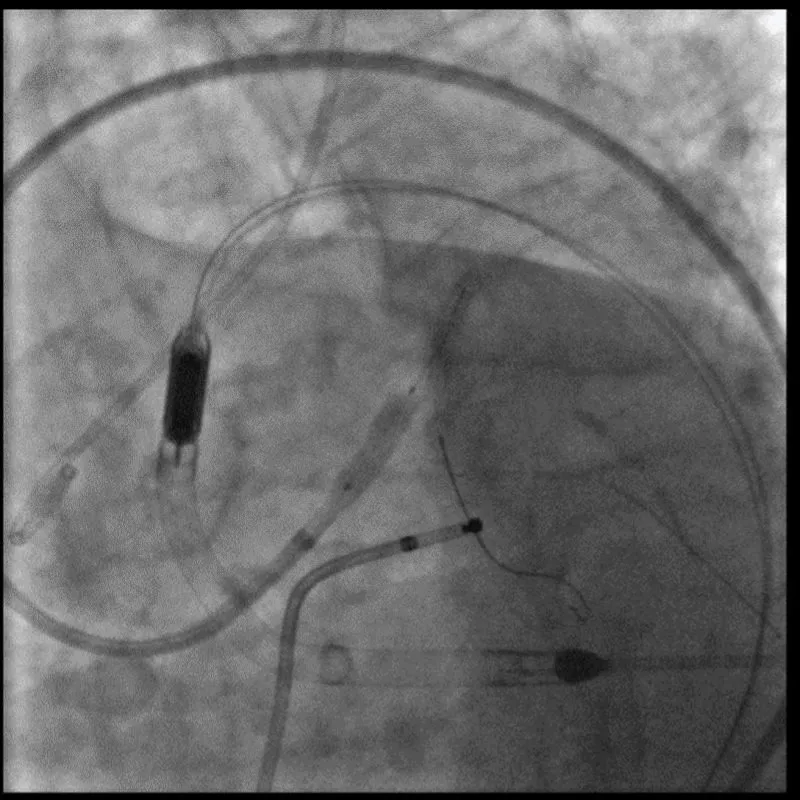

With the support of deep sedation, an angio-guided right femoral access was obtained, and a 12F introducer was advanced. We crossed the aortic valve with an Amplatzer left 1 catheter with a 0.035” wire and exchanged the wire with an extra-stiff Safari. We performed aortic Valvuloplasty with a Nucleus balloon 18 x 40 mm. (Figure 7) Then, we exchanged the wire and advanced an IMPELLA CP device, starting a protected PCI on LM. (Figure 8) An EBU 4.0 catheter was advanced, the stenosis was crossed on the Left Main (LM) and mid-Left Anterior Descending artery (LAD) using a BMW guide wire, and with the aid of a microcatheter a 0.014” Rotawire was positioned, followed by rotational atherectomy using a 1.5 mm burr on LM and mid LAD, (Figure 9) and a 2.0 mm burr on LM alone (Figure 10). This was followed by predilation with a 2.5 x 20 mm SC balloon and the implantation of a 2.5 x 32 mm Synergy drug-eluting stent (Figure 11). Then, the Left Main was predilated with a 3.5 x 12 mm NC balloon, and a 4.0 x 15 mm Xience Sierra drug-eluting stent was implanted and post-dilated with a 4.5 x 8 mm SC balloon (Figure 12). Immediate angiographic control confirmed a successful result. Then we removed the IMPELLA CP device and advanced a 14F e-sheath Edwards on the right femoral artery, crossed the aortic valve with a Safari extra-stiff wire, and performed a Sapien 3 23 mm valve implantation with a good angiographic result (Figure 13). Post-procedural echocardiographic and angiographic assessment confirmed the valve was correctly positioned, with no significant gradient and a minimal residual leak. The procedure was uneventful, and the patient was discharged on the fourth day with triple therapy: Aspirin 100 mg once daily, Clopidogrel 75 mg once daily, and Apixaban 2.5 mg twice daily. At the quarterly follow-up, the patient reported hospitalization for anemia, requiring a transfusion of 3 units of packed red blood cells. Endoscopic exams were negative, and hypochromic, normocytic anemia persisted. Given the patient’s CHA2D2-VASc score of 5, HAS-BLED score of 4, and recent dual Drug-Eluting Stent (DES) implantation, she was admitted for left atrial appendage percutaneous closure. Before this procedure, a repeat coronary angiography showed good results in the previously implanted stents (Figure 14). Subsequently, through a right femoral percutaneous approach using a 12F introducer, a 22 mm Amulet device was positioned for left atrial appendage closure (Figure 15). The procedure was completed without complications. At the 4-year follow-up, the patient presented in good hemodynamic status, with an echocardiographic ejection fraction of 55%. She continued on clopidogrel 75 mg once daily therapy.

Figure 8: Impella CP Device.